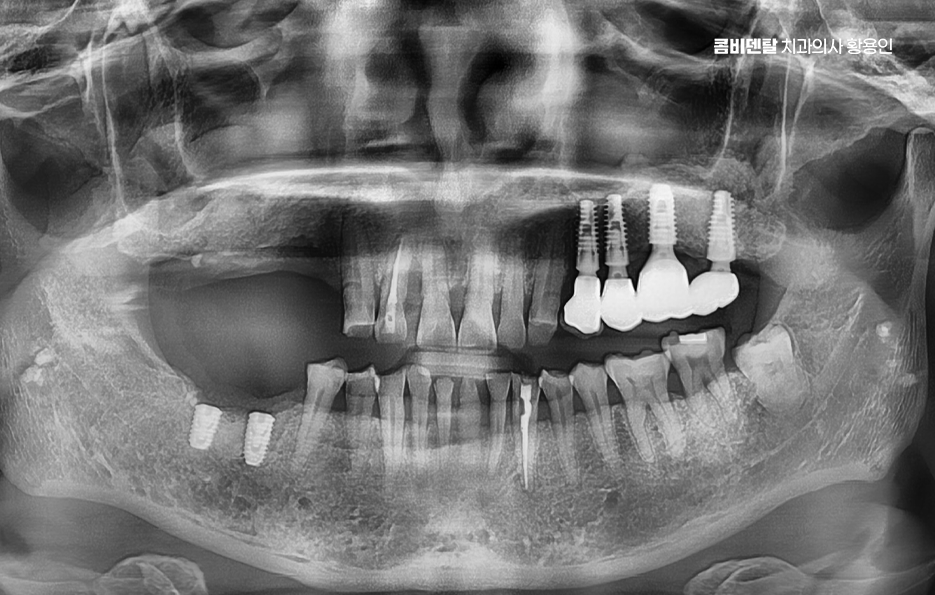

어금니 임플란트 과정에서 수술 당일에는 국소마취 후 잇몸을 절개하거나 최소 절개로 접근해 뼈에 임플란트를 식립하며 수술 후에는 일정 기간 골유착을 기다리는데 임플란트와 뼈가 단단히 결합하는 과정이라 할 수 있었어요

골유착이 완료되면 지대주를 연결하고 본을 떠서 최종 보철물을 제작하며 어금니 크라운은 강도와 교합 조화를 동시에 고려해 제작하는데 씹는 힘이 집중되는 부위이기 때문에 높이와 접촉점 조정이 중요하며 교합이 맞지 않으면 나사가 풀리거나 보철물에 문제가 생길 수 있어서 장착 후에도 교합 점검 및 정기적인 검진, 스케일링 등의 관리가 중요할 수 있어요

흔히 임플란트는 충치가 생기지 않는다고 생각하는 경우가 많은데 잇몸 염증은 충분히 생길 수 있으며 임플란트 주위염이 발생하면 뼈가 녹아 실패로 이어질 수 있어서 치간칫솔이나 치실을 사용해 꼼꼼히 관리하고, 정기 검진을 통해 뼈 상태를 확인해야 하고 특히 어금니는 음식물이 잘 끼는 위치라 더 신경 써야 한다는 점에서도 치료 계획 만이 아니라 유지 관리까지 포함한 장기적인 케어가 중요하다고 볼 수 있었어요